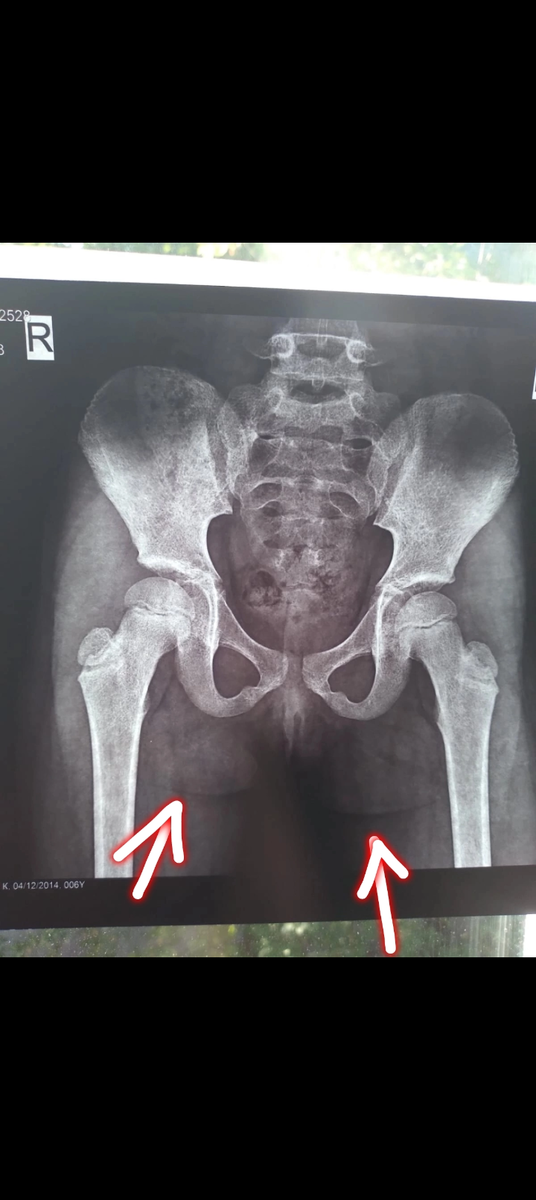

Тазобедренные суставы ребенка с гфф

• Соответствующая рентгенологическая картина (отставание костного возраста, разреженность костной ткани, артрозы, псевдоподагра...)